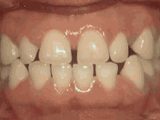

第七种

牙列稀疏,牙槽骨过长,或者牙齿少,导致排列太宽松,零零散散,经过矫正后的是这样的